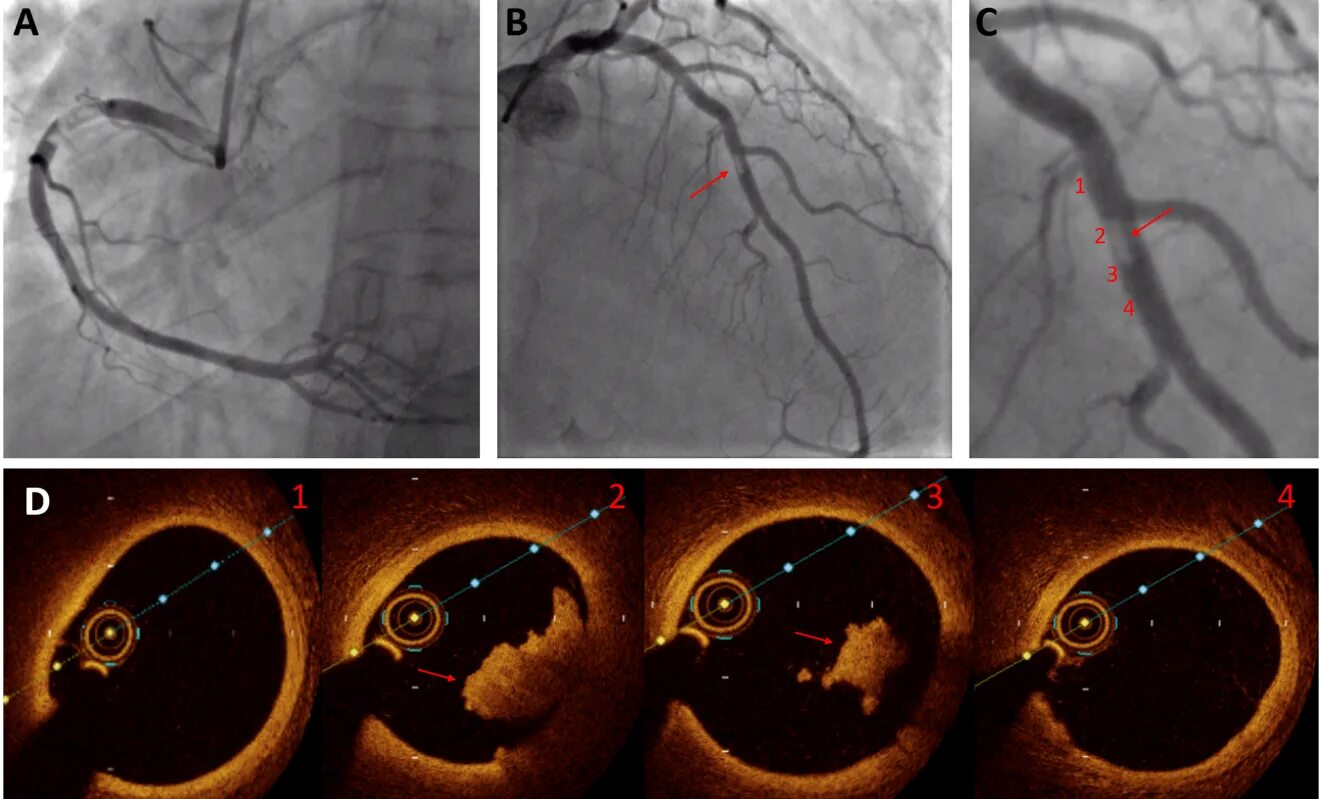

- Сложность диагностики: Ручной поиск таких бляшек на снимках оптической когерентной томографии (ОКТ) требует огромного опыта, занимает много времени и подвержен субъективной оценке.

- Всем пациентам провели сверхточную внутрисосудистую визуализацию (ОКТ) их коронарных артерий.

- Вручную: Независимой экспертной центральной лабораторией (золотой стандарт).

- Автоматически: Алгоритмом ИИ OCT-AID, который был заранее обучен распознавать различные типы тканей в сосуде.